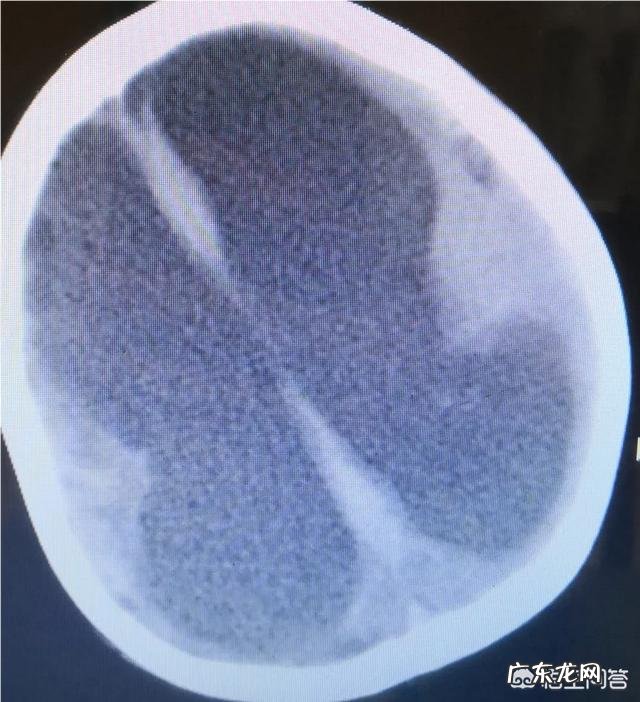

脑出血能恢复到何种程度呢?应该注意些什么呢?这个是丘脑出血破入脑室,在脑室铸型了,特别是由于第四脑室的堵塞,造成脑脊液循环障碍(也就是你那医生讲的不通畅),形成梗阻性脑积水 。

你现在摆的管子起到两个作用,一把不能流动的脑脊液引流出来,二是也可以顺带引走一些出血,促进恢复 。

【脑出血导致一侧偏瘫,能康复吗?】单从片子上出血情况看,估计zhi疗效果会还可以,但是脑出血存在很多不确定性,比如再出血,颅内感染等等都有可能 。